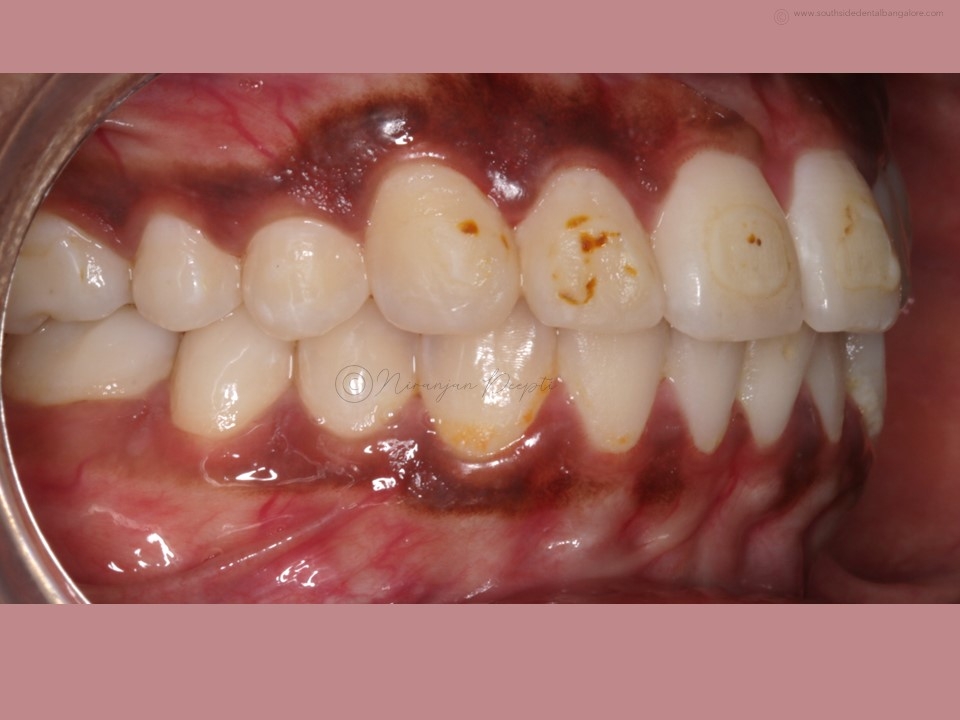

Polishing of teeth after the debonding of braces is a crucial step in the orthodontic treatment process.

- Smoother Surface: Braces leave adhesive residue and small imperfections on the tooth surface. Polishing helps smoothen these areas, reducing the risk of plaque accumulation and making it easier to clean teeth effectively.

- Minimizes Staining: Residual bonding materials and rough surfaces can attract stains, affecting the appearance of your smile. Polishing removes these stains and restores the natural luster of your teeth.

- Scaling: Before polishing, your orthodontist may perform scaling to remove any hardened plaque or calculus deposits that have accumulated during the braces treatment.

- Polishing: Using a specialized dental tool, your orthodontist/dentist will carefully polish each tooth surface to remove any remaining adhesive residue and smooth out imperfections.